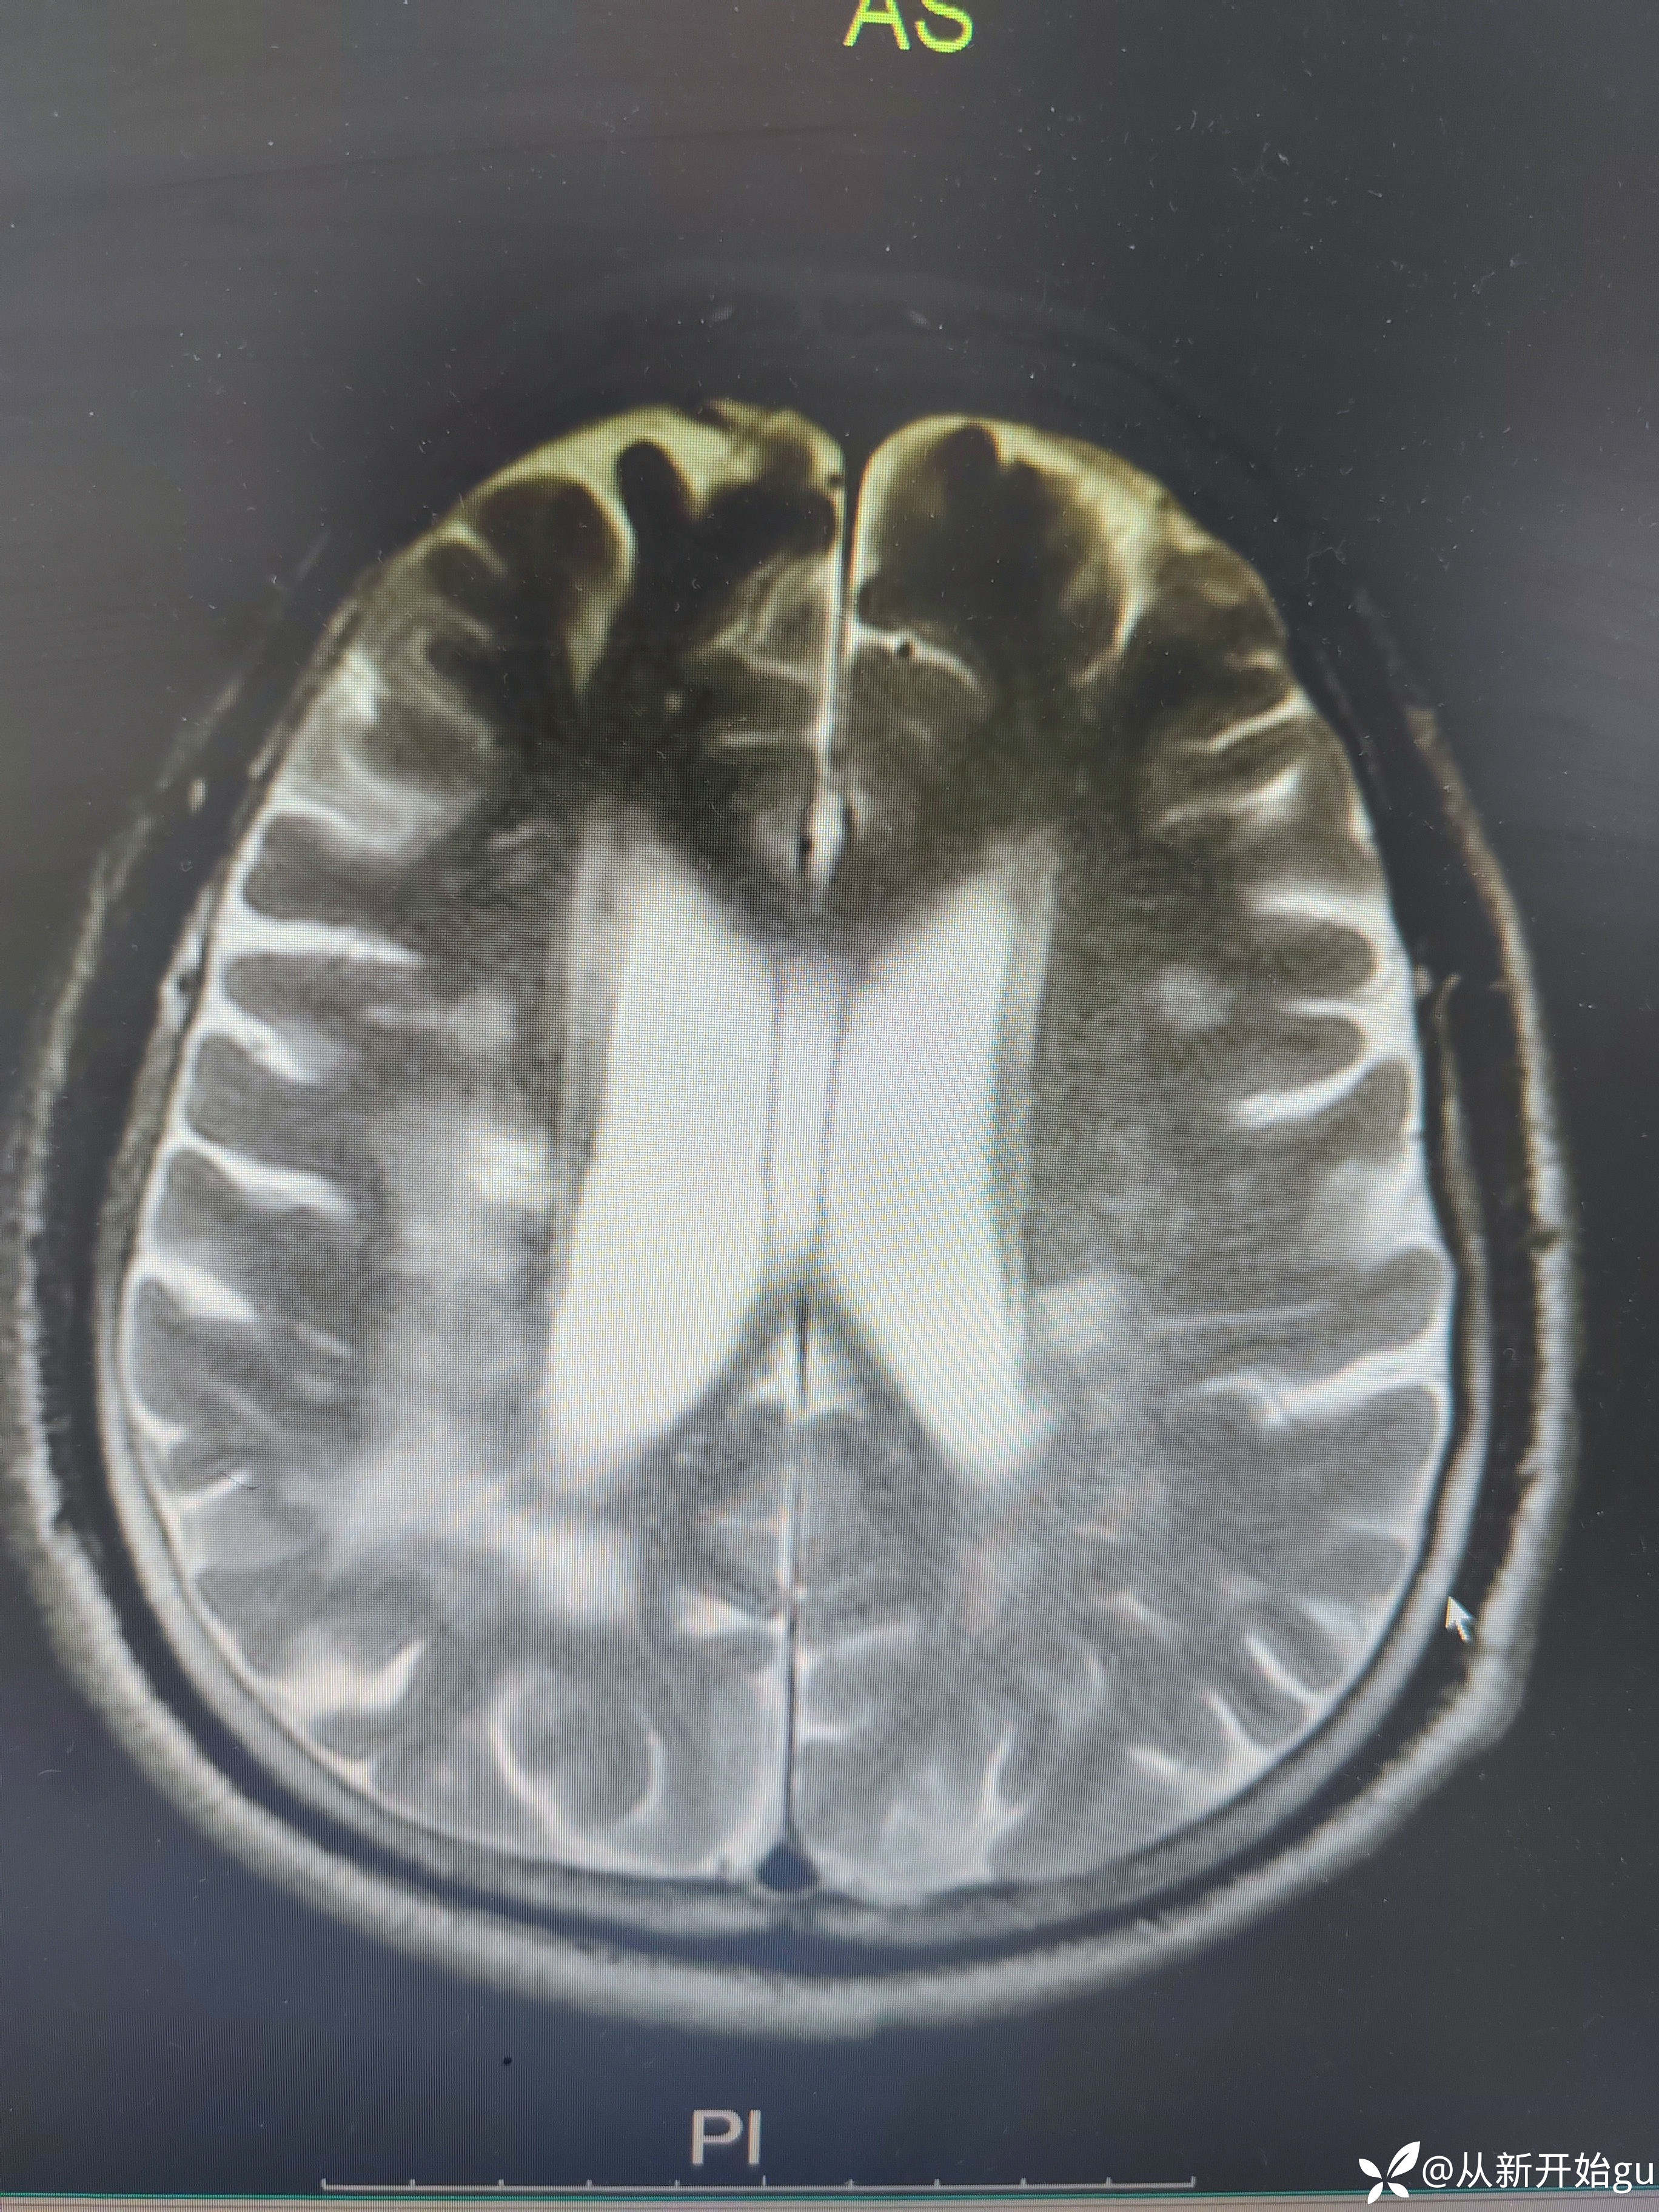

患者男性53岁,主因被发现左下肢活动障碍2.5小时来院,(患者下夜班,于上午9点休息,下午3点醒后出现症状)。既往脑梗死病史9个月,遗留言语不利及口角歪斜的症状。查体:右侧鼻唇沟稍浅,神舌右偏,左侧下肢肌力4级,左侧指鼻试验欠稳准,左侧巴氏征阳性。外院完善颅脑CT无出血改变。来院后完善核磁检查如图所示。